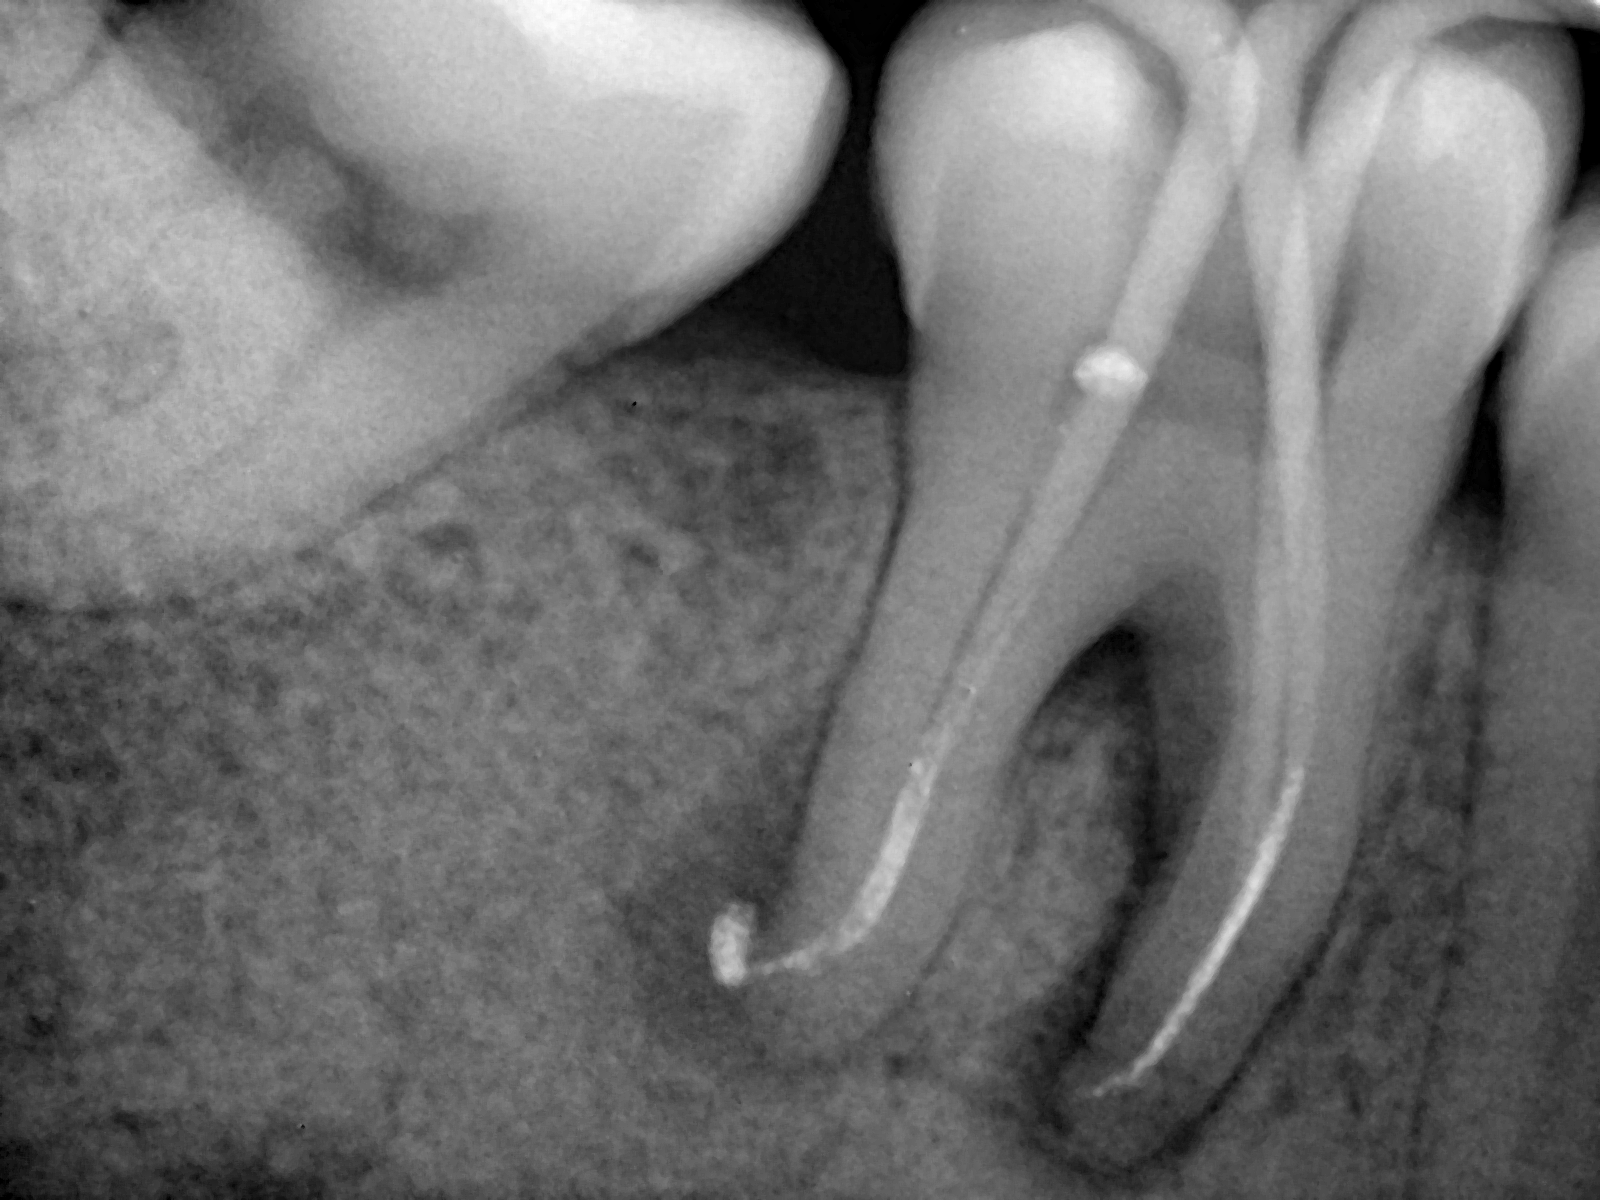

Jangan cabut gigi yang sakit parah! Perawatan Saluran Akar (PSA) adalah prosedur profesional yang menyelamatkan gigi dari infeksi. Kami menawarkan prosedur minim rasa sakit untuk mengobati pulpa gigi, melindungi gigi belakang, dan menghindari pencabutan.